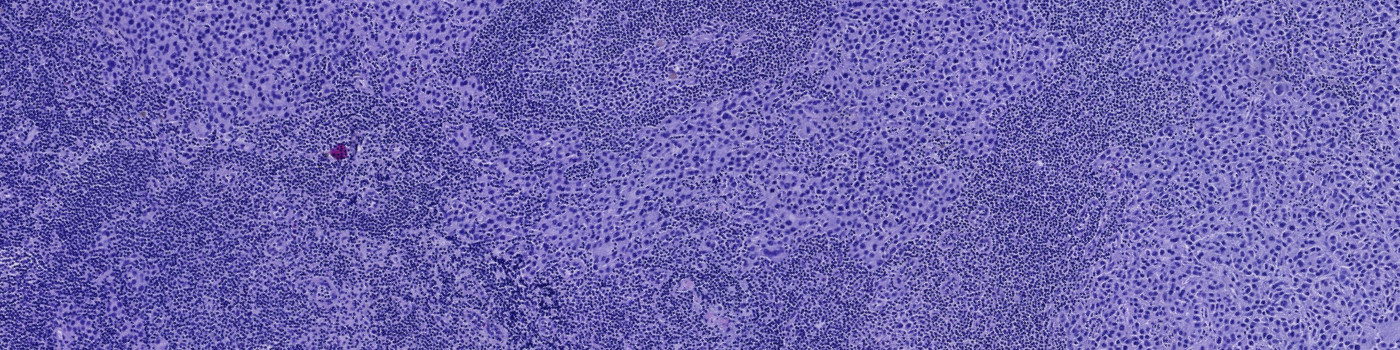

Developed for metastasis detection in H&E stained lymph nodes

Finding metastases in H&E stained lymph node sections can be time consuming and challenging. The differences between small metastases, epithelial tissue and clusters of macrophages are often subtle, and would not be possible to distinguish using conventional image analysis techniques.

This APP utilizes AI/deep learning and has been trained to detect metastases in lymph nodes associated with breast and colon adenocarcinoma, stained with H&E. The deep learning architecture allows it to recognize complex structures and interpret the tissue context when analyzing an image, making it an efficient tool for detecting even small metastases that are not easily noticed.

Step 2: Metastasis Detection: Identifies possible metastases using AI.